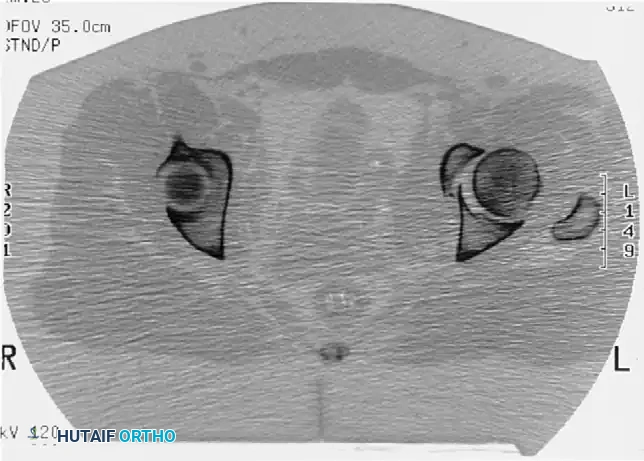

Incarcerated Intra-Articular Fragments

Following the closed reduction of a hip dislocation, a post-reduction CT scan is mandatory. While small avulsions of the ligamentum teres sequestered deep in the cotyloid fossa may be observed, any osteochondral fragment lodged between the articulating surfaces of the femoral head and the acetabular dome necessitates urgent surgical excision and joint irrigation.

In the absence of these emergencies, surgery should be delayed for 3 to 5 days. This window allows for the optimization of the patient's hemodynamic status, resolution of intrapelvic bleeding, and detailed preoperative planning (including 3D CT reconstructions and the assembly of an experienced surgical team). During this delay, the hip should be maintained in skeletal traction to protect the articular cartilage from pressure necrosis.